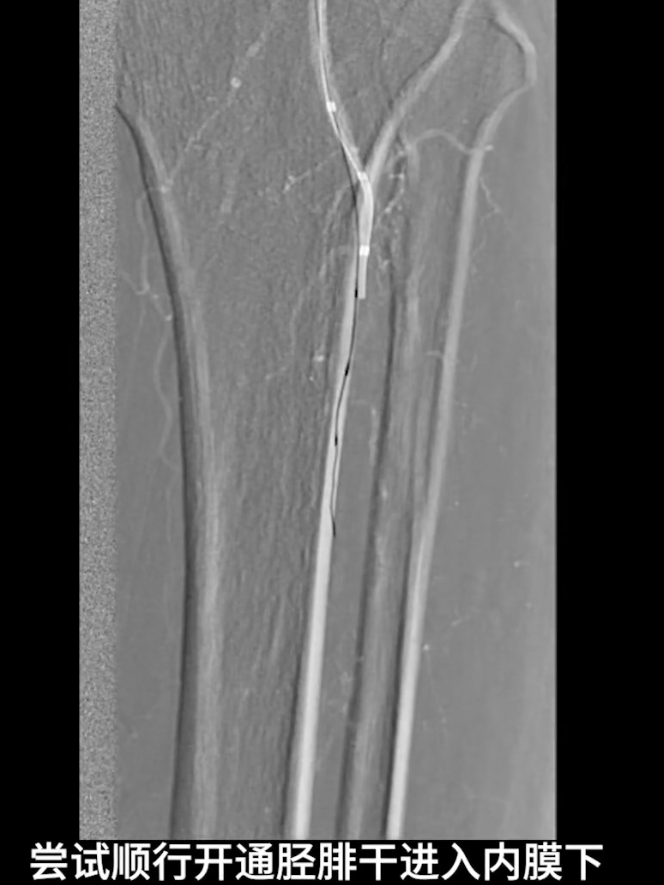

膝下流出道开通

顺行开通尝试:以V18导丝配合支撑导管顺行开通胫腓干,导丝进入内膜下,开通受阻。